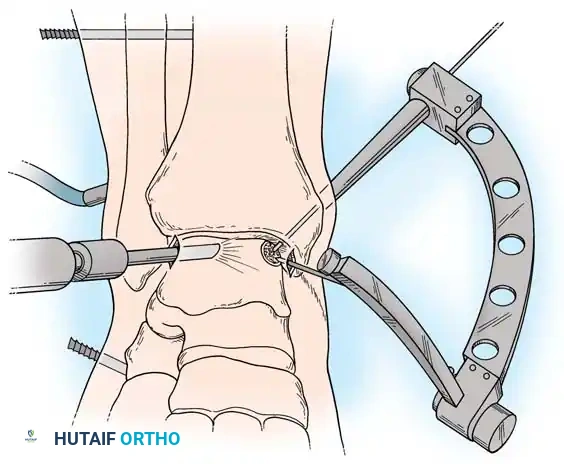

Transmalleolar Portals

As originally described by Guhl, transmalleolar portals are advanced techniques reserved for addressing osteochondral defects of the posterior-central portion of the talus that cannot be reached via standard portals.

Medial transmalleolar portal trajectory.

Lateral transmalleolar portal trajectory.

- Technique: These portals are established 2 to 3 cm proximal to the tip of the medial or lateral malleolus. Under direct arthroscopic visualization from an anterior portal, a 0.062-inch Kirschner wire is inserted using an anterior cruciate ligament (ACL) tibial guide for pinpoint accuracy. The wire is advanced across the malleolus to drill the chondral lesion. The ankle can be dynamically plantarflexed or dorsiflexed to allow drilling of the lesion in various locations.